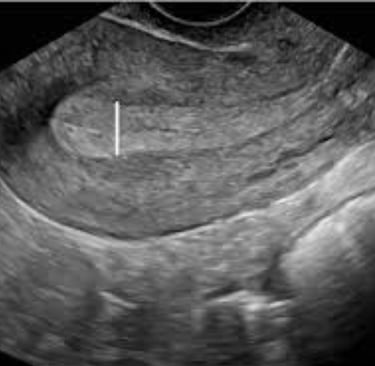

Tıbbi görüntülemede (Transvajinal Ultrason) ölçülen milimetrik değerler, kanser riskini belirleyen en önemli verilerdir:

Postmenopozal kanama ile gelen bir kadında endometrial kanser (EK) olasılığı ("Pre-test Probability") yaklaşık %10'dur. Transvajinal Ultrasonografi (TVUS) ile ölçülen Endometrial Kalınlık (EK), bu olasılığı değiştiren en güçlü belirteçtir.

Senaryo 1: Endometrial Kalınlık ≤4mm (İnce Endometrium)

Negatif Likelihood Ratio (LR−): 0.1 civarındadır.

Yorum: %10 olan kanser riskini, %1'in altına indirir.

Karar: Biyopsi gerekmeyebilir (bireysel risk faktörleri yoksa), takip yeterlidir.

Senaryo 2: Endometrial Kalınlık ≥5mm

Sensitivite: %96, Spesifisite: %60 civarı.

Yorum: Kalınlık arttıkça kanser riski artar, ancak her kalınlık kanser değildir (polip, fibroid olabilir).

Karar: Doku tanısı (Biyopsi/Histeroskopi) zorunludur